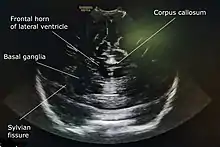

A 5 to 7.5 MHz probe is used to scan deeper structures in the brain. A 7 to 12 Mhz probe is used for scanning superficial structures for detecting lesions between the brain and the skull, superior sagittal sinus thrombosis, cerebral oedema, and evaluating the structures of sulci and gyri.[4]

A standard cranial ultrasound examination usually involves recording of approximately 11 views of the brain from different angles, six in the coronal plane and five in the sagittal and parasaggital planes.[7] This allows all parts of the ventricles and most of the rest of the brain to be visualised.

While the anterior fontanelle is the most commonly used acoustic window for cranial ultrasounds, more advanced operators may gain additional views, especially of posterior fossa structures, by using the mastoid fontanelle, the posterior fontanelle and/or the temporal window.[8]

Other refinements of cranial ultrasound technique include serial measurement of the width of the lateral ventricles ("ventricular index") to monitor suspected ventricular dilatation and colour Doppler to assess blood flow.